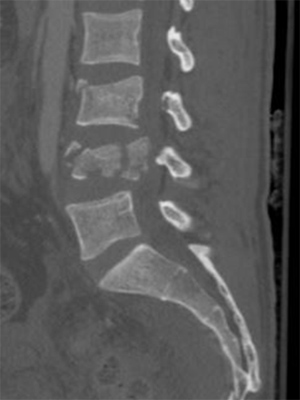

Frattura vertebrale